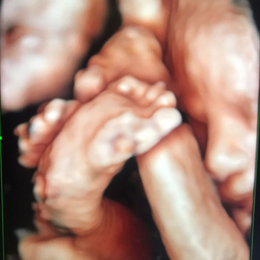

- Las formas nuevas de ecografía pueden proporcionar imágenes en 5-D.

- 1 foto color ampliada en papel fotográfico color tamaño A4.